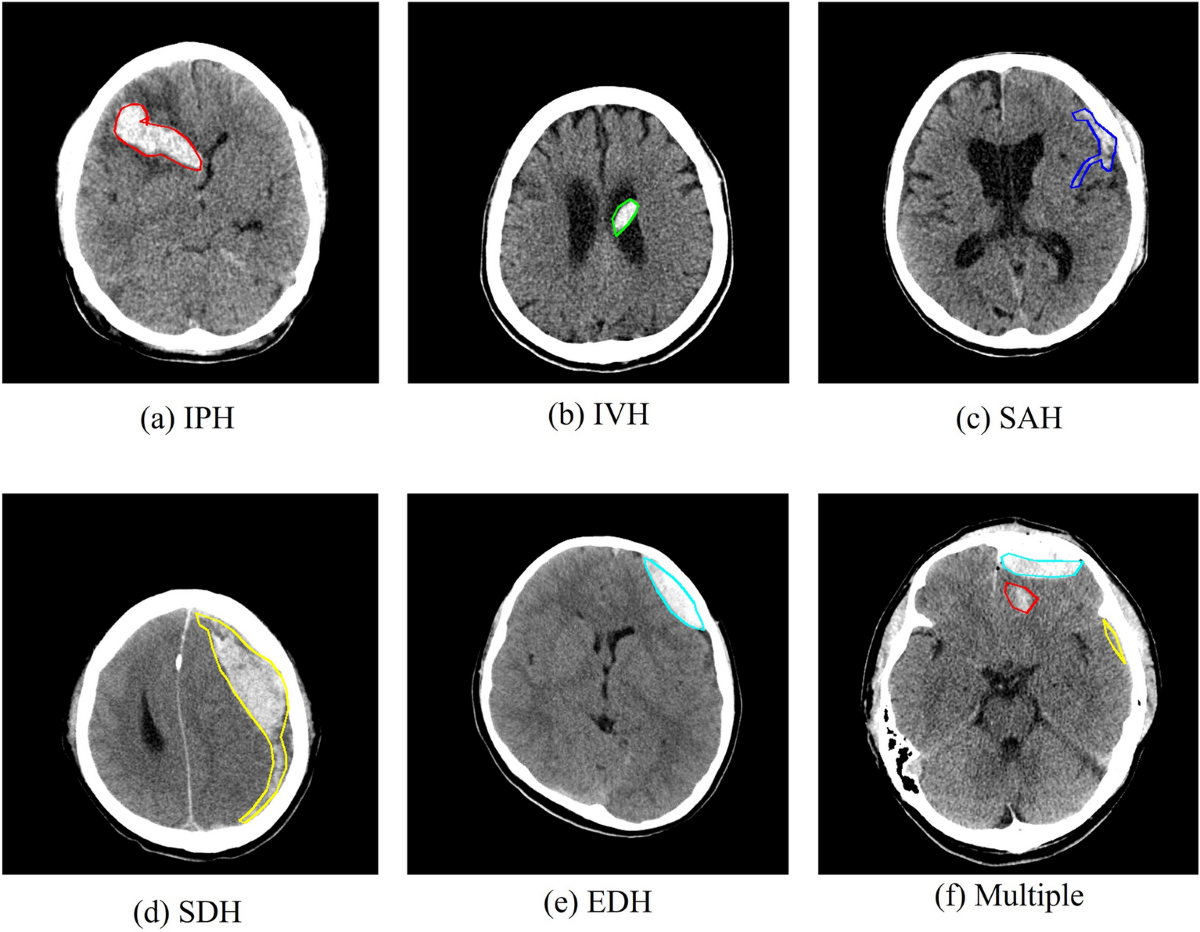

Emergency Triage Of Brain Computed Tomography Via Anomaly Detection With A Deep Generative Model Nature Communications